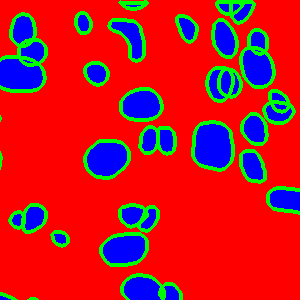

The task of nuclei segmentation can be roughly divided into two stages: the first stage is extracting the foreground(nuclei), the second stage is segmenting the connected foreground area into separated nuclei and finding out the boundary of each nucleus. Our method intends to merge these two steps by extracting the nuclei and their edges at the same time. That is the reason why it is named ”nuclei-boundary(NB) model”. As shown in Fig.3, the output of the NB model has three channels, each has the same height and width with the input image. Its values represent the probabilities of each pixel being , or class, respectively. The manual annotation for our segmentation problem is the boundary of each nucleus. A pixel belonging to the class means that it is on or inside an annotated boundary and within 2 pixel from the boundary. Pixels of the class are those that are inside annotated boundary but are not pixels. Correspondingly, the output can be regarded as an RGB image and the estimated maps of the , and are represented by red, green and blue, respectively, as shown in Fig.3. To generate the ternary mask for training, we apply a morphology operator to each nucleus to obtain the pixels, and then subtract pixels from the nucleus to get pixels.

Figure 6 shows how our method segments the nuclei step by step. The color variety is well controlled by the color normalization procedure. The prediction result shows clear nuclear areas and nucleus boundaries. In the final segmentation result and ground truth image, each nucleus is represented by a different color.